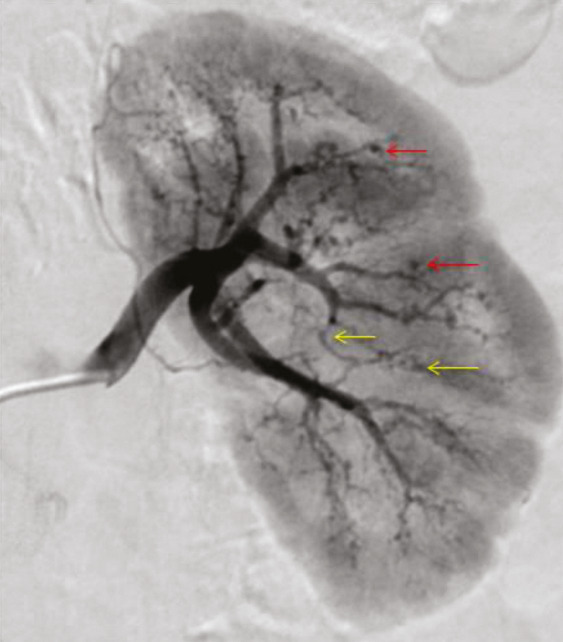

Les atteintes digestives et rénales sont vasculaires, en lien avec des sténoses des moyens vaisseaux, responsables de phénomènes ischémiques et/ou de microanévrismes (fig. 4).6 Leur diagnostic se confirme à l’imagerie, notamment par une angiotomodensitométrie (TDM). L’artériographie, examen de référence, peut s’avérer nécessaire, à visée diagnostique en cas de négativité de la TDM,2 mais surtout à visée thérapeutique, permettant une artério-embolisation en cas d’hémorragie grave.

L’atteinte rénale se manifeste soit par une hypertension artérielle isolée, parfois sévère, soit par une authentique néphropathie vasculaire (insuffisance rénale aiguë, protéinurie tubulaire +/- hématurie microscopique, stigmates biologiques de microangiopathie thrombotique).16 Elle est en lien avec des sténoses, pouvant aussi entraîner des infarctus rénaux. Les microanévrismes des artères rénales et de leurs branches peuvent être responsables d’hématomes sous-capsulaires ou rétropéritonéaux.17 Si l’insuffisance rénale ne se voit que dans 12 % des PAN,5,6 cette néphropathie vasculaire, non glomérulaire, représente un enjeu diagnostique majeur. Contrairement aux autres vascularites, notamment celles ­associées aux anticorps anticytoplasme des polynucléaires neutrophiles (antineutrophil cyto­plasmic antibodies [ANCA]), la biopsie rénale ne doit pas être réalisée avant d’avoir exclu les microanévrismes en artériographie, au ris­que de complications hémorragiques.16,18

L’imagerie artérielle peut suffire à poser le diagnostic, en cas de suspicion clinique et de présence d’anévrismes sacciformes ou fusiformes, de sténoses des artères de moyen calibre, notamment rénales, hépatiques ou digestives.2,4 En première intention, une imagerie non invasive telle que l’angio-TDM ou l’angio-­IRM (en cas de contre-indication aux produits de contraste iodés) est recommandée mais nécessite un regard exercé de la part du radiologue. L’artériographie reste l’examen de référence en cas de doute diagnostique, mais n’est réalisée qu’en deuxième intention, compte tenu d’éventuelles complications, à type d’hématome, de faux anévrismes au point de ponction ou de néphropathie aux produits de contraste.2 Elle peut aussi jouer un rôle thérapeutique, en cas de saignement sévère, permettant de réaliser une embolisation.